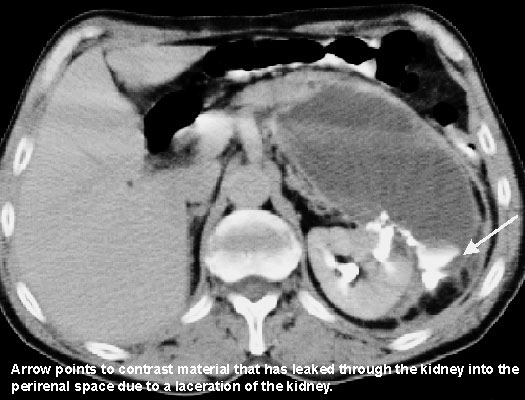

During a football game between two arch rivals, the wide receiver of one team was involved in a pass pattern across the middle of the field. The quarterback was being rushed and threw the pass high. The wide receiver leapt to catch the pass and just as he did so he was "sandwiched" between the cornerback and free safety. The two defensive players hit the receiver just below the ribs on the left side, one in front and one from behind. The receiver managed to hang on to the ball but crumpled to the turf in pain. At first it was thought that he was just "shaken up," but the pain in his flank continued and became more severe. He was taken to the emergency room and examined. His vital signs were slightly elevated, but within normal range. Plain film X-rays showed no broken bones, but the margin of the left psoas major muscle was not distinguishable. Urinalysis showed blood in his urine. An IVP and CT scans were done. The IVP showed leakage of contrast into the tissue immediately around the kidney. The hemorrhage was confined to the area immediately around the kidney and extended medially toward the abdominal aorta. The diagnosis was that the kidney had been lacerated or ruptured. Immediate surgery was performed to close the laceration. The player's season ended, but he recovered uneventfully.

An IVP is an intravenous pyelogram. Iodinated contrast is injected into a cutaneous vein and travels to the kidney where it is concentrated and excreted in the urine. Since the kidney was ruptured the arterial blood leaked into the surrounding tissues and was visible.

The kidney is surrounded by a perirenal fatty capsule, the renal (Gerota's) fascia and pararenal fat. The fat offers no resistance to the hemorrhage, but it was contained in the renal fascia. The renal fascia extends toward the midline and therefore blood was directed toward the abdominal aorta, thus obscuring the margin of the psoas muscle.